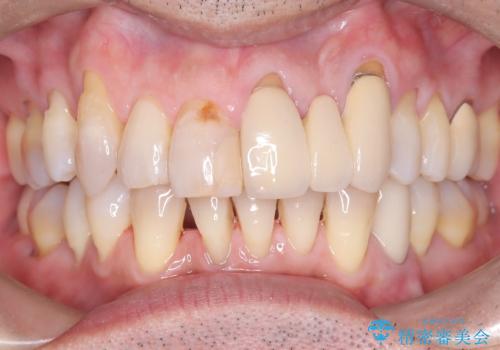

- 50代の患者様で、右上の八重歯と歯並びの乱れを気にされてご来院されました。特に、すでに装着されている前歯のセラミックブリッジを外したくないという強いご希望がありました。精密な検査の結果、八重歯を治すためのスペースが不足しているため、右上の4番目の歯(小臼歯)を抜歯し、そのスペースを利用して歯並び全体を整える治療計画を立案。装置には目立たないインビザラインを採用し、ブリッジを温存しながら八重歯の改善を目指しました。

今回の治療で最も重要だったのは、患者様のご要望通り既存のセラミックブリッジを外さずに矯正を進める点でした。計画通り右上の小臼歯を抜歯し、透明なインビザラインを使用して抜歯スペースを閉じながら、八重歯を正しい位置へ移動させました。ブリッジの形態と調和するに、他の歯の移動を工夫をすることで、複雑な条件をクリア。治療の結果、長年気にされていた八重歯が解消され、見た目が大きく改善しました。50代からでも、ご自身の要望を叶えながら、美しく機能的な歯並びを獲得していただけました。